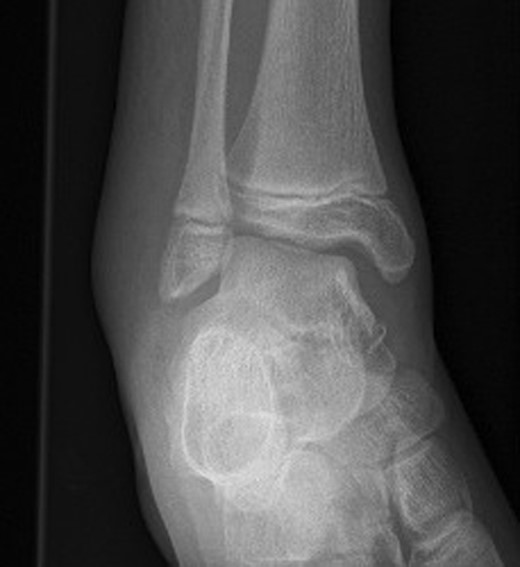

An otherwise fit and well 15-year-old Caucasian male patient, who was cycling down a hill, collided with an obstacle after being ejected over the handlebars of his pushbike. In the Emergency Department, the patient was appropriately triaged according to ATLS protocol which identified isolated closed injuries to his clavicle, and bilateral lower limbs, with no neurovascular compromise [2]. No head or neck injuries were sustained and a secondary survey revealed no other injuries other than some superficial abrasions. Plain radiographs revealed a left undisplaced clavicle fracture, an angulated extra-articular fracture of the left distal tibia and a right ankle talar tilt with no evidence of any bony fracture (Fig. 1). Initial management in the Emergency department included analgesia administration, a collar and cuff for his clavicle fracture and below knee plaster of Paris (POP) backslab for his bilateral lower limb injuries, with strict elevation and neurovascular monitor.

Right ankle plain radiograph demonstrating talar tilt and increased medial tibio-talar joint space.